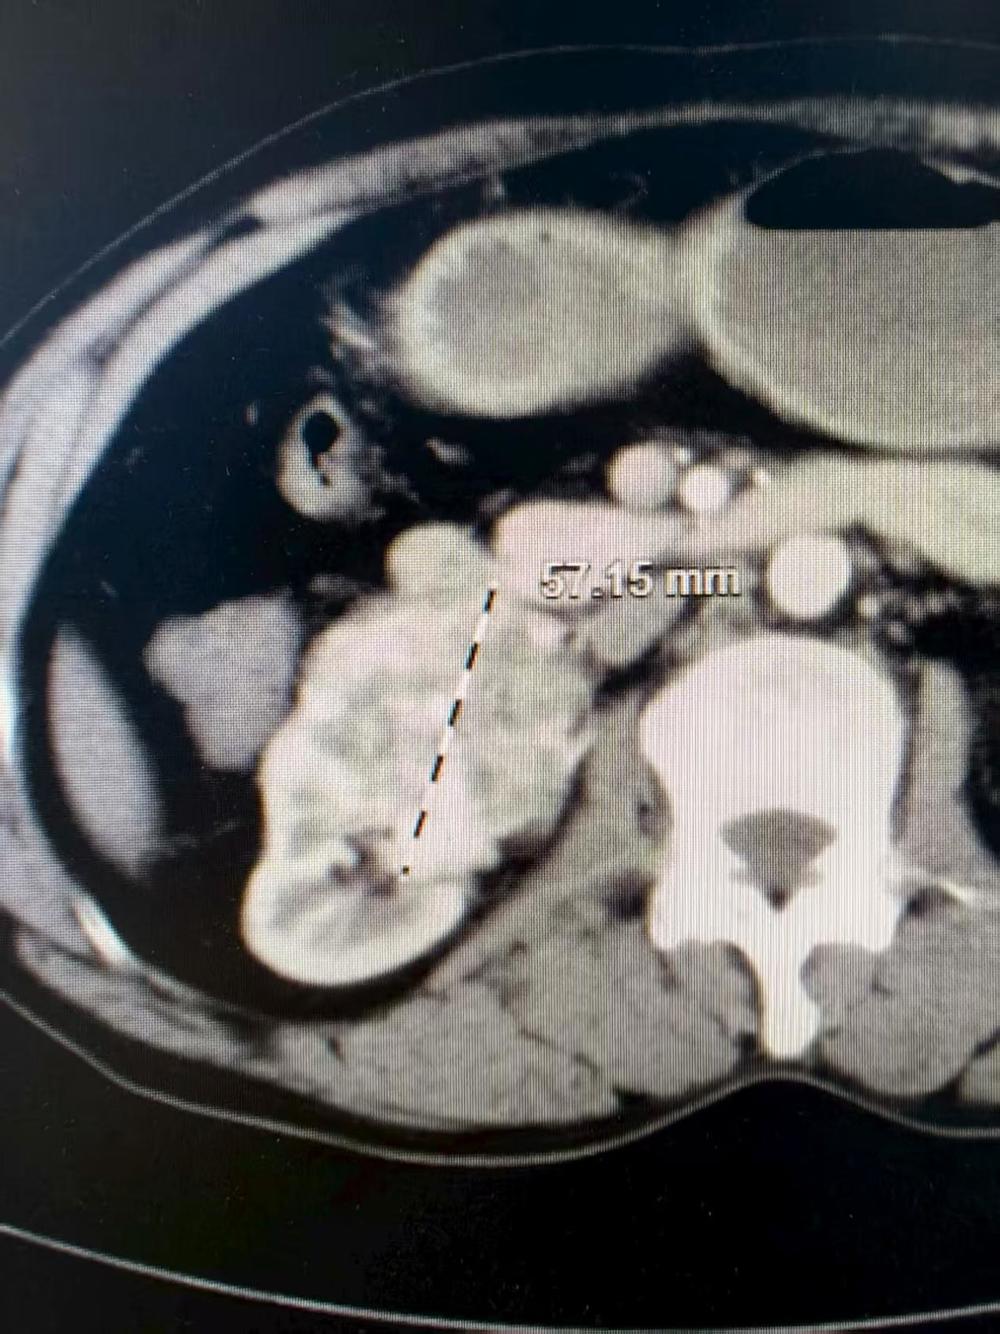

患者黄大叔因为反复的右腹部隐痛2年,今年8月份来我院检查发现右肾中下极有一个直径超过5.5厘米的肿瘤,初步诊断为肾癌。如果使用传统的开放式手术,需要切开长达15-20厘米的切口,创伤大、出血多、术后恢复时间长。

CT图片